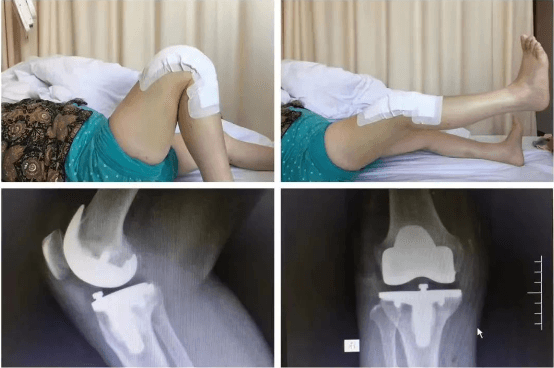

清晨剛上班的骨科門診,來(lái)了幾位復(fù)診患者,分別是肩袖損傷術(shù)后、髕骨脫位術(shù)后、膝關(guān)節(jié)前交叉韌帶斷裂重建術(shù)后,膝關(guān)節(jié)半月板撕裂修復(fù)縫合術(shù)后的患者?;颊咭?jiàn)到李鵬主任立即都非常熱情的迎了上來(lái),李主任也耐心的進(jìn)行了接診,并一一為患者詳細(xì)、專業(yè)的進(jìn)行術(shù)后康復(fù)指導(dǎo)?;颊咚邮苁中g(shù)的肩、膝關(guān)節(jié),活動(dòng)范圍明顯改善,他還為患者擬定下一階段的康復(fù)動(dòng)作計(jì)劃,繼續(xù)進(jìn)行主被動(dòng)鍛煉,肌力訓(xùn)練,日常生活行為能力訓(xùn)練等動(dòng)作。診療完成后李主任讓患者添加微信,每周拍自己的康復(fù)鍛煉視頻發(fā)給自己,以便對(duì)患者的動(dòng)作及時(shí)進(jìn)行指導(dǎo)。這一舉動(dòng)立即讓患者及家屬感受到了作為醫(yī)生的良苦用心,他說(shuō):“要讓患者挺直腰桿走回家”。這幾位復(fù)診患者都有一個(gè)共同特點(diǎn),就是他們受傷后都接受了運(yùn)動(dòng)醫(yī)學(xué)亞??频年P(guān)節(jié)鏡微創(chuàng)手術(shù),手術(shù)后3-5天即可出院,創(chuàng)傷小、恢復(fù)快,他們對(duì)手術(shù)效果非常滿意。

通過(guò)不斷的學(xué)習(xí)國(guó)際國(guó)內(nèi)前沿的理論知識(shí),李鵬帶領(lǐng)亞專業(yè)團(tuán)隊(duì)醫(yī)護(hù)人員,在我院較早提出術(shù)前康復(fù)及無(wú)痛病房的理念,將EARS理念融入于患者術(shù)前、術(shù)中、術(shù)后治療過(guò)程中,通過(guò)與麻醉科合作,圍手術(shù)期的管理及手術(shù)技術(shù)的不斷提高,實(shí)現(xiàn)術(shù)后幾乎無(wú)痛。在臨床醫(yī)學(xué)中,骨科手術(shù)和康復(fù)是相輔相成的,他帶領(lǐng)團(tuán)隊(duì)術(shù)前即開(kāi)始正規(guī)的運(yùn)動(dòng)康復(fù),保證患者手術(shù)成功,促使患者術(shù)后有效、快速地恢復(fù),早日回歸生活、重返運(yùn)動(dòng)。

擅長(zhǎng)治療各種骨關(guān)節(jié)外傷、骨關(guān)節(jié)疾病。手術(shù)方面擅長(zhǎng)髖、膝關(guān)節(jié)置換術(shù)、膝關(guān)節(jié)單髁置換術(shù)、脛骨高位截骨術(shù)、股骨頸骨折及轉(zhuǎn)子間骨折等手術(shù)。富血小板血漿(PRP)治療骨關(guān)節(jié)炎。擅長(zhǎng)關(guān)節(jié)鏡下膝關(guān)節(jié)交叉韌帶重建、半月板損傷縫合、髕骨脫位、肩袖修補(bǔ),肩峰撞擊征、鈣化性肌腱炎,肱二頭肌長(zhǎng)頭腱炎,髖關(guān)節(jié)盂唇損傷、髖關(guān)節(jié)撞擊征、踝關(guān)節(jié)不穩(wěn)、踝關(guān)節(jié)韌帶損傷、肩關(guān)節(jié)不穩(wěn)、肩周炎、各類關(guān)節(jié)內(nèi)骨折、關(guān)節(jié)脫位的手術(shù)治療。